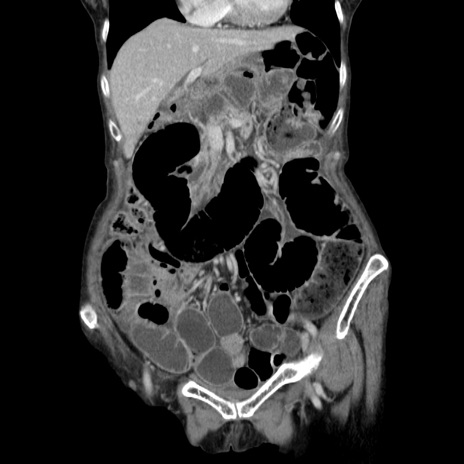

横断像

【症例】80歳代女性

【主訴】胸のつかえ感

【現病歴】約9時間前に食後から胸のつかえた感じあり、嘔吐あり、来院。

【既往歴】胃癌(全摘)、胆摘、虫垂炎

【身体所見】心窩部に圧痛あり、反跳痛なし。

【データ】WBC 5700、CRP 0.05